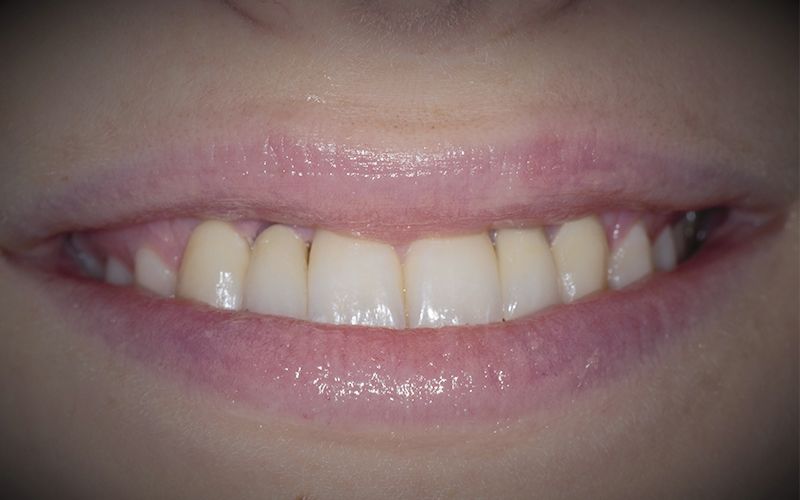

Al cabo de unos días se hicieron los controles clínicos y radiológicos pertinentes y se procedió a cementar las dos coronas de forma definitiva dando por finalizada la rehabilitación por agenesia de los dos incisivos laterales 12 y 22.

El sistema Biomimetic Pearl permite tratar casos unitarios con limitación de espacio de una forma mínimamente invasiva y con una rehabilitación final que cumpla las expectativas tanto funcionales como estéticas de nuestros pacientes.